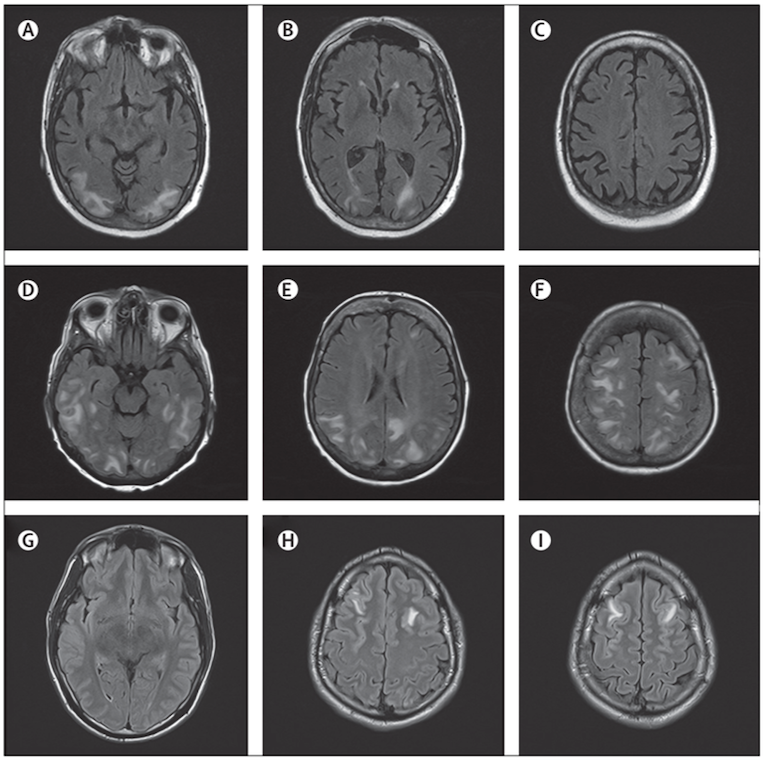

A ulteriore approfondimento, è stata eseguita una RM encefalo con riscontro di multiple aree di alterato segnale a livello corticale localizzate bilateralmente agli emisferi cerebrali con reperto prevalente a destra in regione frontale e parietale e con coinvolgimento, a questo livello, della sostanza bianca e in assenza di segni di impregnazione patologica di mezzo di contrasto, reperti radiologici compatibili con leucoencefalopatia posteriore reversibile (PRES).

Approfondendo l’anamnesi con i caregiver è emerso un consumo abituale e continuativo di liquirizia da parte del bambino negli ultimi mesi prima del ricovero. Inoltre, alla misurazione della PA durante la degenza, è stata riscontrata un’ipertensione arteriosa di stadio II (PA >95esimo percentile) senza danno d’organo a livello cardiologico, renale e retinico. L’ipertensione riscontrata ha necessitato di politerapia antipertensiva con ACE-inibitore (captopril), diuretico (acetazolamide) e calcio-antagonista (amlodipina) per ottenere un buon controllo pressorio. Inoltre, il paziente non ha più presentato episodi critici ed è stato riscontrato un netto miglioramento del quadro radiologico alla RM encefalo eseguita a 14 giorni di distanza.

La sindrome da leucoencefalopatia posteriore reversibile (PRES) è una sindrome clinica e radiografica a eziologia eterogenea caratterizzata da sintomi neurologici acuti di disfunzione cerebrale associati ad anomalie caratteristiche al neuroimaging nella sostanza bianca e grigia cerebrale posteriore (Figura).

Al neuroimaging (preferibilmente RM con immagini pesate in diffusione) si riscontra tipicamente un edema vasogenico localizzato bilateralmente a livello della sostanza bianca negli emisferi cerebrali posteriori, in particolare nelle regioni parieto-occipitali, ma l’interessamento è variabile3.